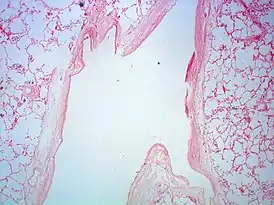

В артерио-венозных мальформациях, чаще всего, отсутствует капиллярная сеть, вследствие чего осуществляется прямое шунтирование крови из артериального бассейна в систему поверхностных и глубоких вен.